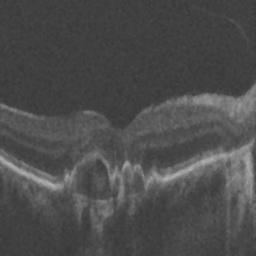

The qualitative results of the proposed system is shown in the Fig. 3. The detection task is evaluated using Area Under the Curve(AUC) metric and the segmentation task is evaluated using Dice Coefficient(DC) metric and the results are presented in Table1

| (a) De-noised OCT slice | (b)Predicted fluid region | (c)Manual fluid segmentation |

| (d) De-noised OCT slice | (e)Predicted fluid region | (f)Manual fluid segmentation |

| (g) De-noised OCT slice | (h)Predicted fluid region | (i)Manual fluid segmentation |

| (j) De-noised OCT slice | (k)Predicted fluid region | (l)Manual fluid segmentation |

| (m) De-noised OCT slice | (n)Predicted fluid region | (o)Manual fluid segmentation |